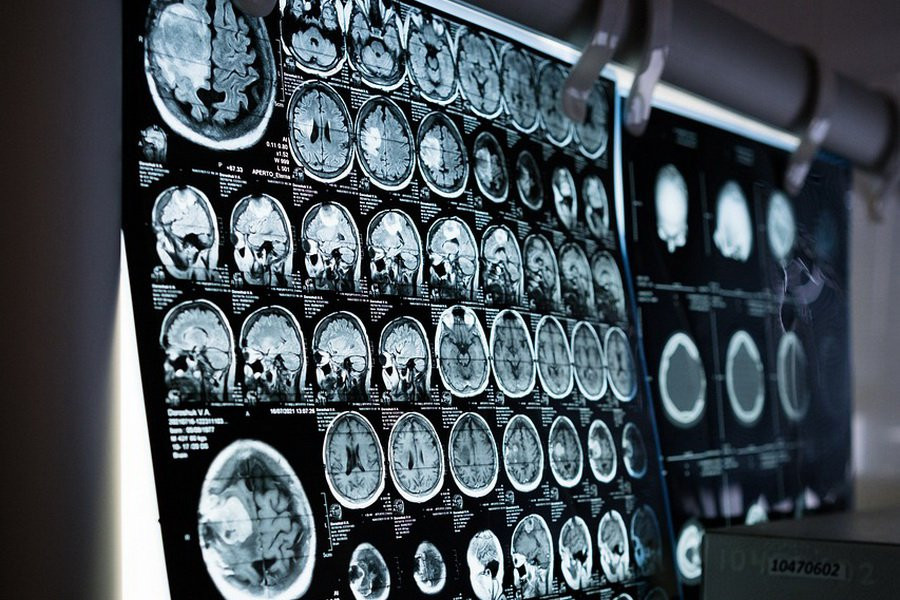

Создание первой автономной системы глубокой стимуляции мозга стало результатом длительных наблюдений за 17 добровольцами, страдающими болезнью Паркинсона. Участникам исследования были имплантированы электроды в глубинные области мозга, что позволило ученым отслеживать изменения в работе нервной системы во время различных повседневных действий как при наличии стимуляции, так и без нее.

В ходе исследования были выявлены характерные изменения в работе гамма-ритмов в моторной коре мозга и в ядре субталамуса, которые возникали в периоды наиболее выраженных симптомов заболевания. Среди этих симптомов были брадикинезия (замедленная реакция конечностей на желание совершить движение), дистония (непроизвольные сокращения мышц) и другие проявления болезни Паркинсона.

На основе полученных данных ученые разработали алгоритм, анализирующий изменения уровня активности этих двух областей мозга и подбирающий оптимальный режим работы устройства. Это позволяет избежать как чрезмерного возбуждения нервных клеток, так и недостаточной их стимуляции.